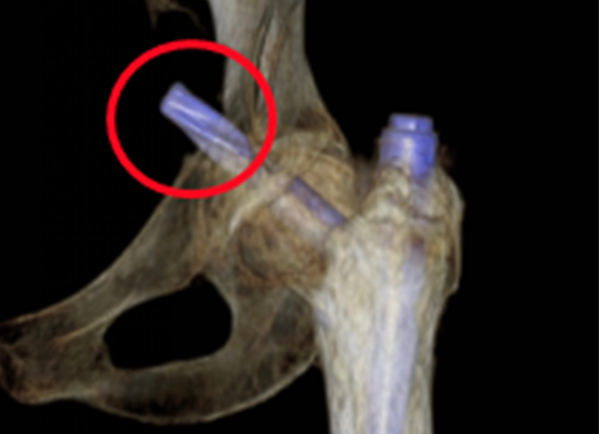

"老人骨质疏松严重,又有低血糖、心脏问题,千万小心再次跌倒!"出院时医生的叮嘱言犹在耳。然而7月的一天,邱婆婆再次摔倒——这次是右侧髋部着地,剧痛让她瞬间无法站立。更糟的是,检查发现不仅骨盆骨折,此前植入的固定钢钉竟因冲击力穿破股骨头刺入盆腔!

"情况比想象中凶险得多。"主刀医生尹一然教授解释,这枚"跑偏"的钢钉紧邻大血管,稍有不慎就会引发大出血;而老人除了高龄,还合并骨质疏松、重度贫血、肾功能不全、心脏问题等16种基础疾病,手术风险极高。

8月8日,一场精密的"生命保卫战"打响。由骨科尹一然教授领衔,联合麻醉科、心血管内科、肾内科等专家制定方案:既要取出刺入盆腔的钢钉,又要解决髋臼缺损和骨量流失难题,还要确保新关节稳固。

先小心翼翼取出嵌在盆腔的钢钉,避免损伤血管;